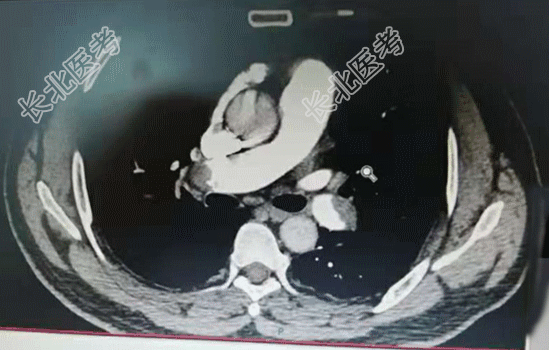

【现病史】2天前,患者无明显诱因出现右侧胸痛不适感,伴呼吸费力。当时无咳嗽、咳痰、发热等症状。以为是劳累导致的症状,经休息后症状缓解不明显,今晨起疼痛症状加重,家属拨打120急救送入我院,急诊科查指脉氧98%,行肺部CTA检查时指脉氧降至92%,肺部CTA显示:肺栓塞。诊断为:肺栓塞。发病以来饮食、睡眠差、小便正常,大便未解,体重无明显变化。

【辅助检查】肺部CTA显示:肺栓塞。心电图:标3、Avf、V₄-V₆导联T波改变。